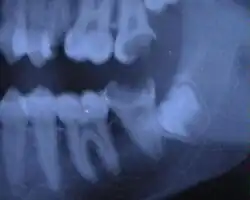

Zähne sind hochgradig widerstandsfähig gegen zerstörerische Umwelteinflüsse, deshalb sind sie die am häufigsten gefundenen Fossilien von Primaten. Ihre Größe und Form, die Dicke ihres Zahnschmelzes und das Verhältnis der beiden stabilen Kohlenstoff-Isotope 12C und 13C im Zahnschmelz (vergl. Isotopenuntersuchung) können Auskunft geben über die stammesgeschichtliche Zugehörigkeit ihrer ehemaligen Besitzer, über ihr Sozialverhalten und ihre Nahrung. Allerdings sind gerade diese Gewebe sowie die ebenfalls widerstandsfähigen Kiefer „besonders anfällig für Homoplasien“[101] (für parallele, unabhängige Entstehung) als Folge ähnlicher Ernährungsweisen, was ihren Nutzen für taxonomische Fragestellungen begrenzen kann.

Der schon bei Homo erectus nachweisbare evolutive Trend zur Verkleinerung der Zähne wurde als eine Folge des Gebrauchs von Steinwerkzeugen interpretiert, mit deren Hilfe die Nahrung zerkleinert wurde, was wiederum die Kaulast von Zähnen, Oberkiefer und Unterkiefer reduzierte.[102]

Verkleinerung der Eckzähne

Der Mensch und die anderen Menschenaffen gehören zu den Altweltaffen. Deren früheste bekannte Vertreter – wie beispielsweise Aegyptopithecus – trugen zwei große, längliche Eckzähne im Oberkiefer, die durch stetiges Reiben an jeweils einem Vorderbackenzahn des Unterkiefers (durch Honen) geschärft wurden. Zugleich wies der Oberkiefer zwei Zahnlücken (Diastema) zwischen Eck- und Schneidezähnen auf, in die jeweils einer der Eckzähne des Unterkiefers passte. Im Verlauf der Hominisation wurden die Eckzähne kleiner und die Zahnlücke im Oberkiefer verschwand.

Ein zweiter, langfristiger evolutionärer Trend, der mit der Verkleinerung der Zähne und der Schnauze einherging, kann aufgrund der Verringerung der Zahnzahl rekonstruiert werden. Weitgehend anerkannt ist heute, dass die ursprünglichen Höheren Säugetiere in jeder Kieferhälfte drei Schneidezähne, einen Eckzahn, vier Vorderbackenzähne und drei hintere Backenzähne hatten. Ihre Zahnformel lautet demnach 3 • 1 • 4 • 3, ihre Zahnzahl betrug 44.[107] Alle heute lebenden Altweltaffen haben hingegen die Zahnformel 2 • 1 • 2 • 3 und somit 32 Zähne. Bei den Menschen ist der Trend zur Verringerung insofern unmittelbar zu beobachten, als der dritte (hintere), so genannte Weisheitszahn erhebliche Unterschiede der Form sowie des Durchbruchzeitpunkts aufweist und seine Zahnanlagen gelegentlich völlig fehlen; er kann daher als Rudiment bezeichnet werden.

Ebenfalls verringert hat sich im Verlauf der Hominisation die Anzahl der Zahnwurzeln, mit denen die Vorderbackenzähne im Kiefer verankert sind: Die frühen Arten der Hominini aus der Gruppe der Australopithecinen hatten zwei Wurzeln pro Vorderbackenzahn, Homo sapiens besitzt nur eine Wurzel.[108] Im Vergleich zu den Schimpansen ist bei den Menschen zudem während der Individualentwicklung der Wechsel vom Milchgebiss zum Dauergebiss verzögert, was zugleich als Indiz für eine Verlängerung der Jugendphase beim Menschen gilt. Bei den nicht-menschlichen Menschenaffen beginnt der Durchbruch der Dauerzähne im Alter von 3,0 bis 3,5 Jahren,[107] beim Menschen hingegen meist erst im 6. Lebensjahr; Ursache ist eine verzögerte Bildung der Zahnwurzeln.[109][110] Ein weiteres Merkmal des jungen Homo sapiens ist, dass der Molar M1 und der Schneidezahn I1 des Dauergebisses gemeinsam durchbrechen, gefolgt vom Schneidezahn I2, während beim jungen Schimpansen zunächst nur der Molar M1 durchbricht, gefolgt von beiden Schneidezähnen.[111][112]

Die schon von Charles Darwin auf veränderte Gewohnheiten bei der Nahrungsaufnahme zurückgeführte Verkürzung des Unterkiefers wurde 2011 durch eine Studie an elf heute lebenden Populationen bestätigt. Ihr zufolge haben Jäger und Sammler längere und schmalere Unterkiefer als Sesshafte, die sich von Feldfrüchten, Milcherzeugnissen oder Zuchttieren ernähren.[113]